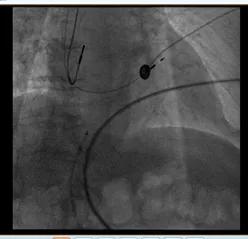

起搏器手术过程中的影像资料

文章图片